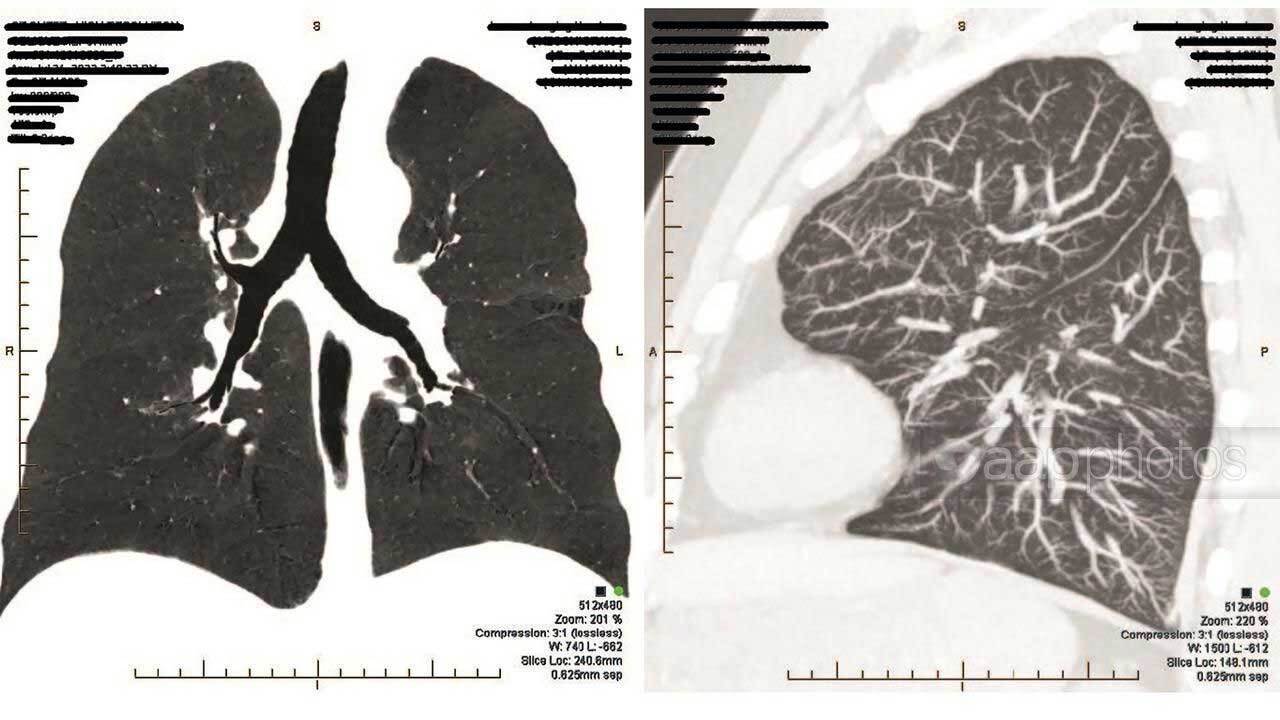

Keogh, who was diagnosed with pneumoconiosis in 2018 and has battled mental-health issues since, was awarded $3.2 million in damages.

Judge David Russell was convinced Keogh's respiratory and psychiatric health meant he would never be able to work again, with evidence suggesting his respiratory condition will deteriorate.

"Mr Keogh cannot work in any job where he would be exposed to even the most minimal level of dust … he most certainly cannot and should not be allowed to work in his old occupation as a plant operator," he said in his judgment on Thursday.